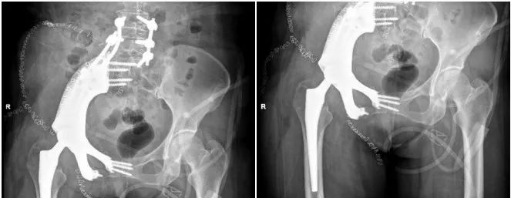

术前影像

术后影像

日前,安医大一附院骨病骨肿瘤外科胡勇教授团队成功完成一例复杂骨盆Ⅰ+Ⅱ+Ⅲ+Ⅳ区肿瘤切除与3D打印组配式半骨盆假体重建手术。患者为女性,53岁,下腰痛半年余,右侧臀部膨隆,右侧下肢轻度浮肿。右侧髂棘髂窝及臀部可触及巨大肿物,压痛明显,右髋外展前屈活动受限,右侧大腿感觉麻木,右足感觉运动正常。骨盆肿瘤切除重建是骨科专业中难度极大、风险极高的手术。骨盆肿瘤约占原发骨肿瘤的3%~4%,其中以软骨系统肿瘤最为多见,其次为骨巨细胞瘤、成骨肉瘤等,儿童尤文肉瘤亦好发于骨盆。

据主刀医师徐生林介绍,本例病例将整个右侧半骨盆Ⅰ+Ⅱ+Ⅲ+Ⅳ区(累及骶骨)进行整块切除,同时切除肿瘤覆盖的部分骶骨。3D打印假体所有骨接触界面均设计为骨整合结构,有利于骨长入和骨盆假体的永久稳定。耻、坐骨结构不规则,因此设计组配式结构,有利于术中操作,极大地方便了术中的假体安装。